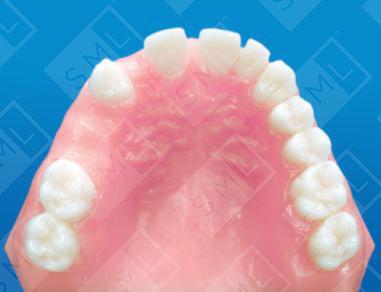

Treatment partials can facilitate some minor tooth movement prior to placing final restorations. In this example, denture teeth are replacing the right lateral and the two bicuspids. Springs are being used to close the anterior diastema and make room for the lateral. Once this has been accomplished, veneers and traditional crown and bridge will be completed to enhance the patient’s function and appearance.